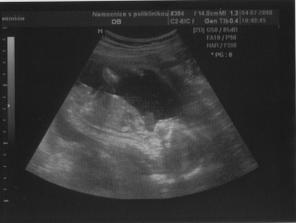

Na kontroly jsem chodila každé 3 týdny a vesměs jsem žádné problémy neměla.. Ze začátku žaludek mírně na vodě,což úderem 12.tt skončilo a já si to začla naplno užívat.. V 17.tt mi začalo celkem dost tvrdnout bříško a hned při další kontrole jsem to řekla doktorovi a ten mě raději poslal na UTZ,byla jsem 18+4,na utz čekala 2 hodiny a měla jsem hroznej strach,zda je všechno v pořádku,doktorovi se to totiž vůbec nelíbilo.. Na UTz bylo vše v tom nejlepším pořádku a zjistili jsme,že čekáme chlapečka - Honzíčka,od začátku těhu jsem to tušila a od začátku mu také Honzíčku říkala,jen manža mu furt říkal Natálko,si ještě vzpomínám,jak moc mě to rozčilovalo 😀

O týden později nás čekal utz ve 20.tt,opět moc krásný zážitek,Honzík se opět ukázal v celé své kráse..